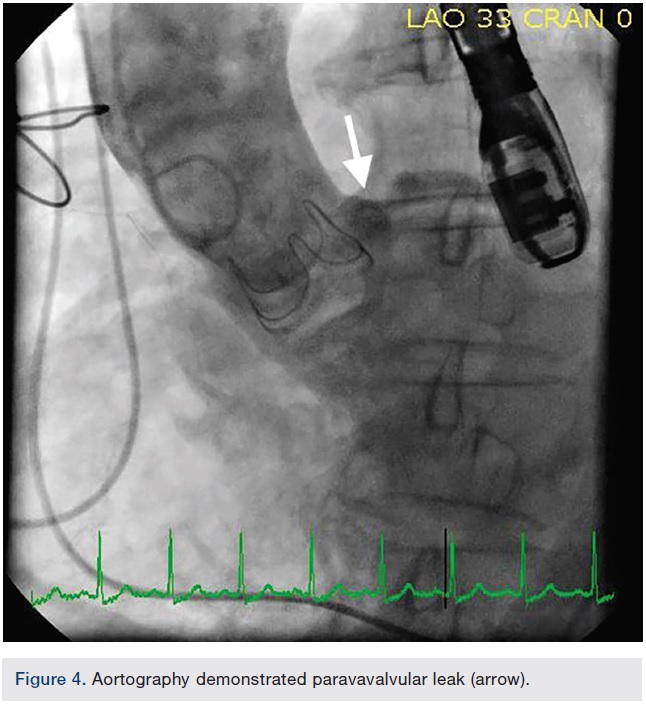

The paravalvular regurgitation began near the left main coronary ostium and extended anteriorly, measuring approximately 1.25cm long and .67cm wide (Figure 3A-B). Both right femoral and right radial accesses were obtained using a 6 French sheath. The aortography, performed via a right radial approach, also demonstrated the paravalvular leak (Figure 4). After crossing the PVL with a .035-inch Glidewire (Terumo Interventional Systems), the guide catheter was unable to advance through the PVL over the .035-inch Glidewire, despite multiple attempts via the femoral approach with different catheters. Attempts were made using a 6 French multipurpose guide catheter, a 5 French Judkins right (JR)4 guide catheter, a mother-daughter technique with a multipurpose guide and a diagnostic catheter, a 6 French, 90cm Destination sheath (Terumo), and a 5 French, 90cm Ansel sheath (Cook Medical).